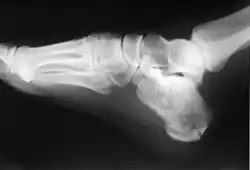

In humans and many other primates, the calcaneus (/kælˈkeɪniəs/; from the Latin calcaneus or calcaneum, meaning heel;[1] pl.: calcanei or calcanea) or heel bone is a bone of the tarsus of the foot which constitutes the heel. In some other animals, it is the point of the hock.

In humans, the calcaneus is the largest of the tarsal bones and the largest bone of the foot. Its long axis is pointed forwards and laterally.[2] The talus bone, calcaneus, and navicular bone are considered the proximal row of tarsal bones.[3] In the calcaneus, several important structures can be distinguished:[3]

There is a large calcaneal tuberosity located posteriorly on plantar surface with medial and lateral tubercles on its surface. Besides, there is another peroneal tubercle on its lateral surface.[2] On its lower edge on either side are its lateral and medial processes (serving as the origins of the abductor hallucis and abductor digiti minimi). The Achilles tendon is inserted into a roughened area on its superior side and the cuboid bone articulates with its anterior side. On its superior side there are three articular surfaces for the articulation with the talus bone.[2] Between these superior articulations and the equivalents on the talus is the tarsal sinus (a canal occupied by the interosseous talocalcaneal ligament). At the upper and forepart of the medial surface of the calcaneus, below the middle talar facet, there is a horizontal eminence, the talar shelf (also sustentaculum tali).[2] Sustentaculum tali gives attachment to the plantar calcaneonavicular (spring) ligament, tibiocalcaneal ligament, and medial talocalcaneal ligament. This eminence is concave above, and articulates with the middle calcaneal articular surface of the talus; below, it is grooved for the tendon of the flexor hallucis longus; its anterior margin gives attachment to the plantar calcaneonavicular ligament, and its medial margin to a part of the deltoid ligament of the ankle-joint.

The calcaneus is part of two joints: the proximal intertarsal joint and the talocalcaneal joint. The point of the calcaneus is covered by the calcanean bursa.